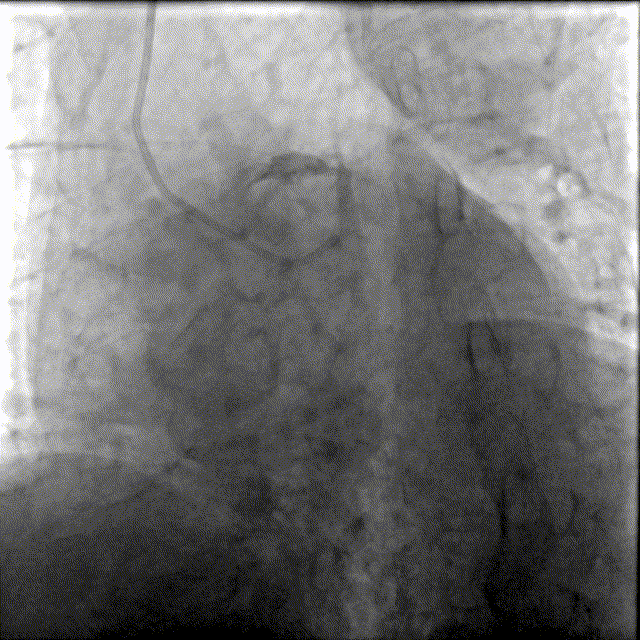

造影如下

患者左主干前三叉1,0,1型病变,主干末端偏心40%狭窄;前降支病变自开口延续至中段,口部80%狭窄,中段80%狭窄,病变位置钙化严重;回旋支近段约30%轻度狭窄,第一及第二钝缘支开口80%局限病变。